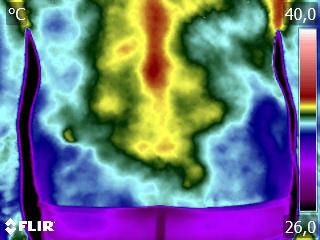

Como no caso do termograma abaixo de abaixo de uma paciente, do sexo feminino, 51 anos, sem comorbidades e que apresentou dor em posterior de coxa após atividade física. Foi realizado um Exame Termofuncional e detectado alterações térmicas condizentes com o relato de dor.

Através dos conhecimentos e estudos da Técnica Termofuncional, foi verificado que estas alterações estavam associadas ao comprometimento da muscular da cadeia posterior, permitindo determinar a causa da dor.

Isso somente foi possível pelo estudo e conhecimento da Técnica Termofuncional, pois ela possui um procedimento reprodutível e escalável.